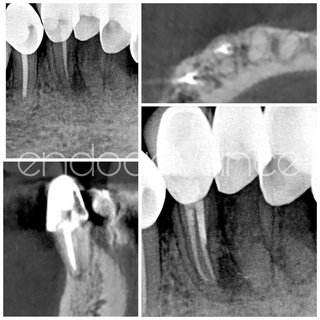

Αρχική ενδοδοντική θεραπεία σε άνω γομφίο με περίπλοκη ανατομία